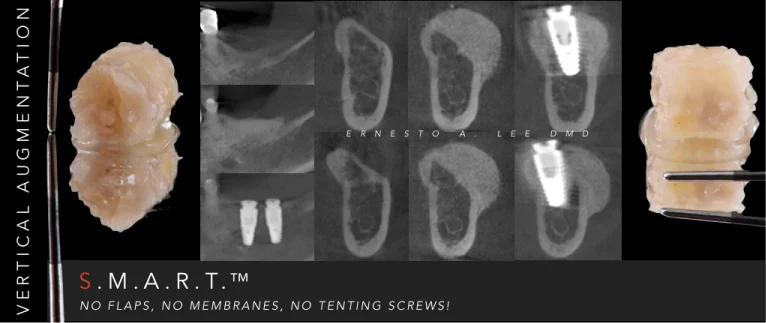

S.M.A.R.T. VERTICAL & HORIZONTAL AUGMENTATION

Performed in a single office procedure using local anesthesia and two small incisions. No flaps, no tenting screws and no membranes were utilized. Sufficient horizontal and vertical bone volume was achieved to allow future placement of multiple implants.

bone-graft-smart

Substantial vertical augmentation in the area of the failed anterior implants accomplished with the S.M.A.R.T. method.  The patient reported minimal pain and moderate swelling. Periosteal elevation was difficult due to extensive scar tissue.